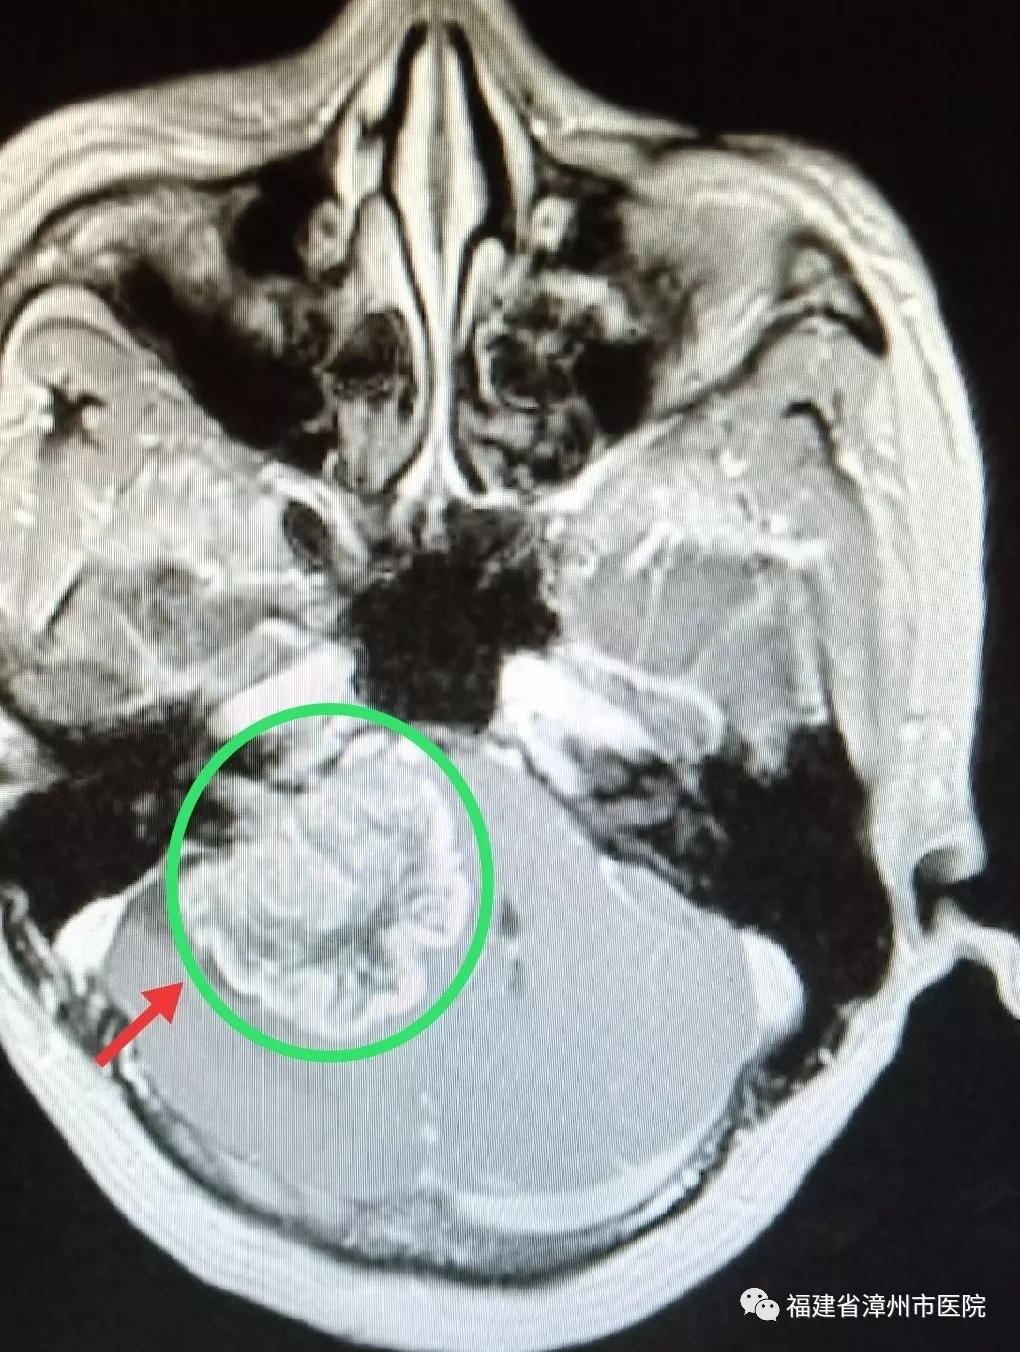

术前(肿瘤)

不久前到漳州市医院神经外科接受了颅内肿瘤切除手术的陈先生就是这种情况。陈先生今年52岁,由于做秘书工作,每天要接听数十个电话,工作压力大,情绪高度紧张。最近,打电话时他总听不清对方讲话,右边耳朵像有蜜蜂在飞,发出嗡嗡的声音。陈先生以为是手机信号不好,更换了手机,依然不奏效。有一次,他无意改用左耳听电话,感觉音质清楚了很多,这才意识到可能是自己耳朵出了问题。陈先生来到漳州市医院检查听力,我告诉他右侧听力明显下降,做磁共振检查后发现颅内有一个直径约5厘米的肿瘤,并且已经严重压迫脑干,并引起脑积水。我询问病史得知,原来4年前陈先生就感觉右耳听力下降,感觉有些耳背,他以为是工作压力大所致,一直没在意。

陈先生因为忽视,延误了最佳治疗时机。当检查发现时,肿瘤已经有5厘米大小,伴有多颅神经损害如轻微面瘫、面部麻木等症状及脑积水存在,脑干重度压迫移位。经过显微神经外科手术,目前已切除肿瘤,顺利出院。